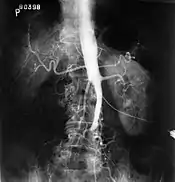

The physical examination usually shows weakened femoral pulses and a reduced ankle-brachial index. The diagnosis can be verified by color duplex scanning, which reveals either a peak systolic velocity ratio ≥2.5 at the site of stenosis and/or a monophasic waveform. MRA and multidetector CTA are often used to determine the extent and type of obstruction. Another technique is digital subtraction angiography which allows verification of the diagnosis and endovascular treatment in a single session.[1]

Angiography provides important information regarding the perfusion and patency of distal arteries (e.g. femoral artery). The presence of collateral arteries in the pelvic and groin area is important in maintaining crucial blood flow and lower limb viability. However, angiography should only be used if symptoms warrant surgical intervention.[1]